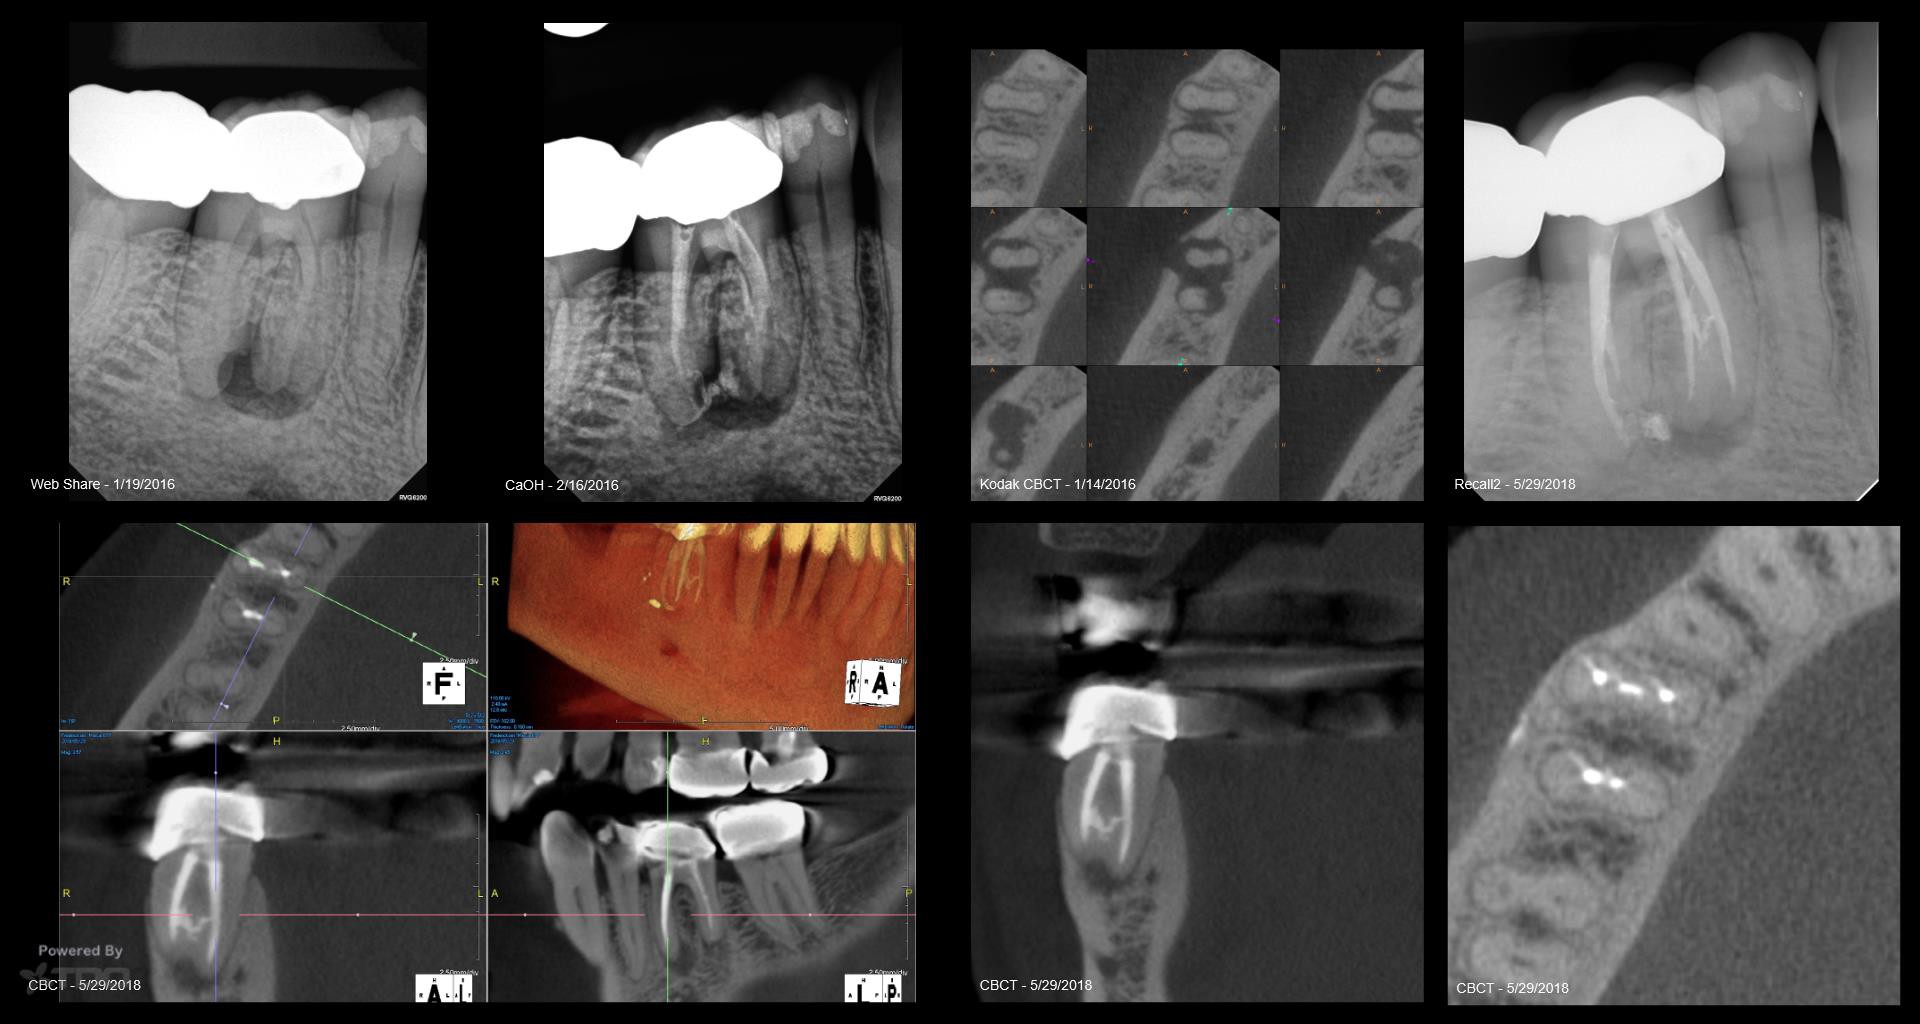

Anoth 15 mo CaOH

1 Yr CBCT Recall